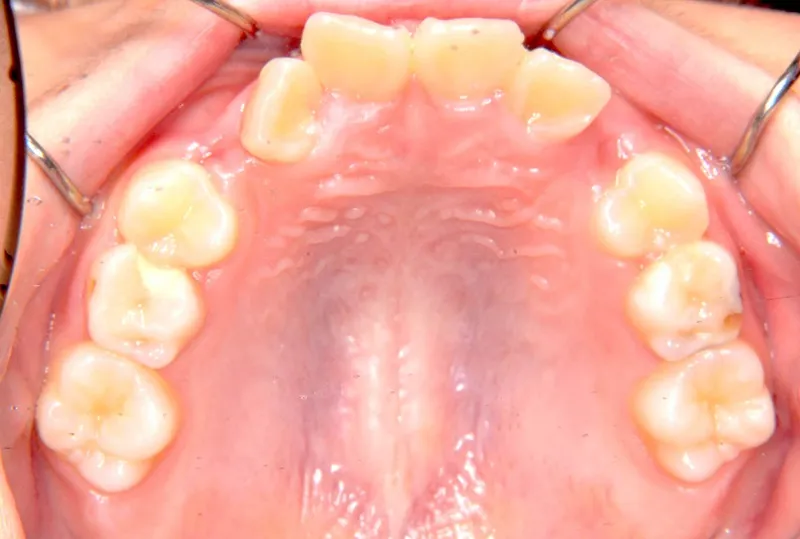

【子供の矯正(一期)】叢生・前歯がゆがんでいる・犬歯の生える隙間がない・9歳女児【M.O】

初診時年齢 小学校3年生 (女性) 主訴 前歯がゆがんでいる・犬歯の生える隙間がない

診断名 叢生 装置名

上下がガタガタで犬歯の生えるすきまがありません。

このままだと犬歯の生えるスペースがありません。放っておくと犬歯が上の位置からはえ、牙のようになってしまいます。

乳歯があるうちは上下オリジナル固定装置を利用し、永久歯が生えそろったらマルチブラケット装置を利用して治療しました。